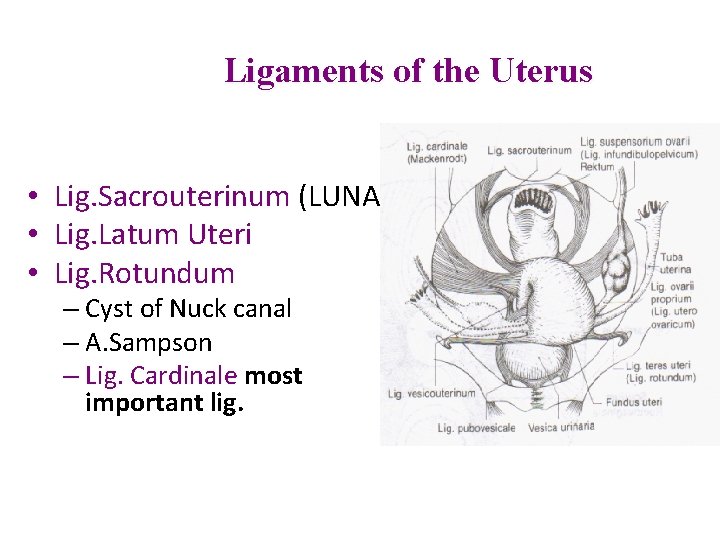

Ligaments of the Uterus • Lig. Sacrouterinum (LUNA) • Lig. Latum Uteri • Lig. Rotundum – Cyst of Nuck canal – A. Sampson – Lig. Cardinale most important lig.